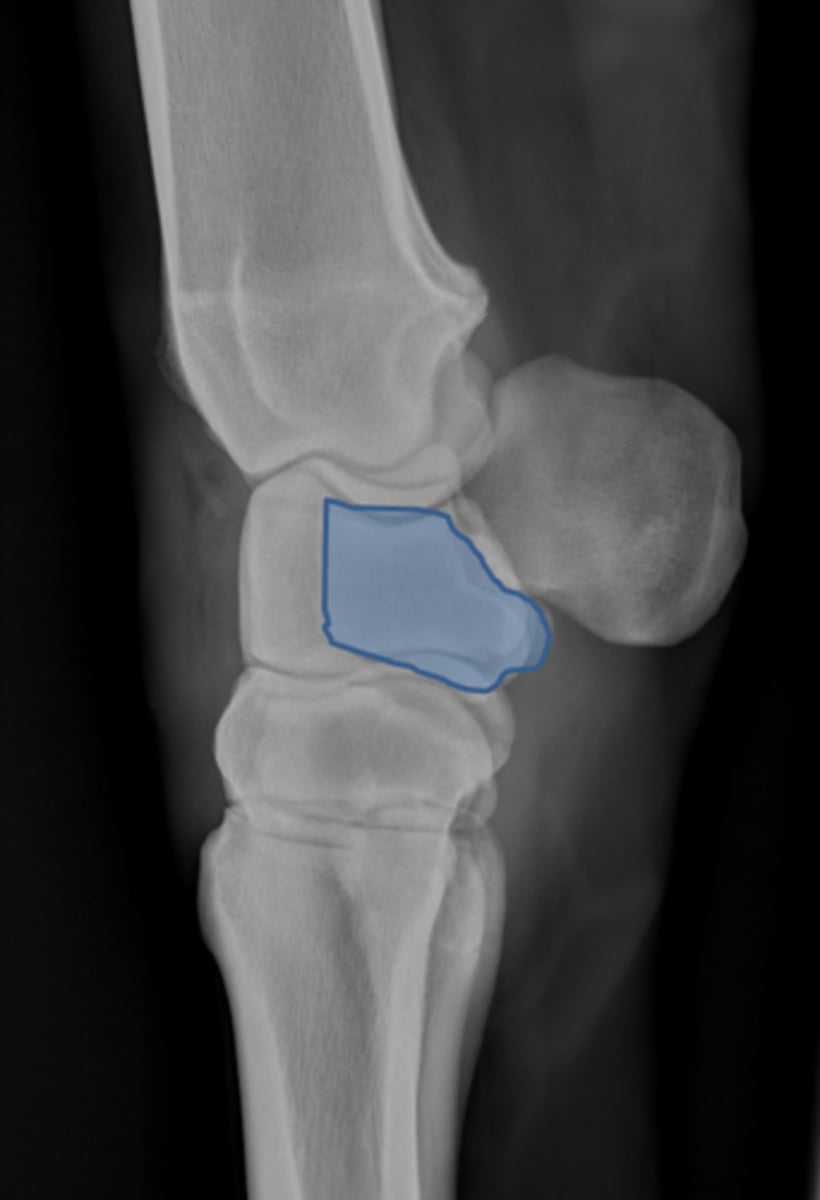

Pastern joint, LM

ID joint and view

Short pastern (P2)

Long pastern (P1)

Pastern joint (proximal interphalangeal joint)

Distal sesamoidean ligament

Long pastern (P1)

Short pastern (P2)

Medullary cavity

Collateral ligament of the coffin joint

Nutrient foramen of P2

Extensor process of P3